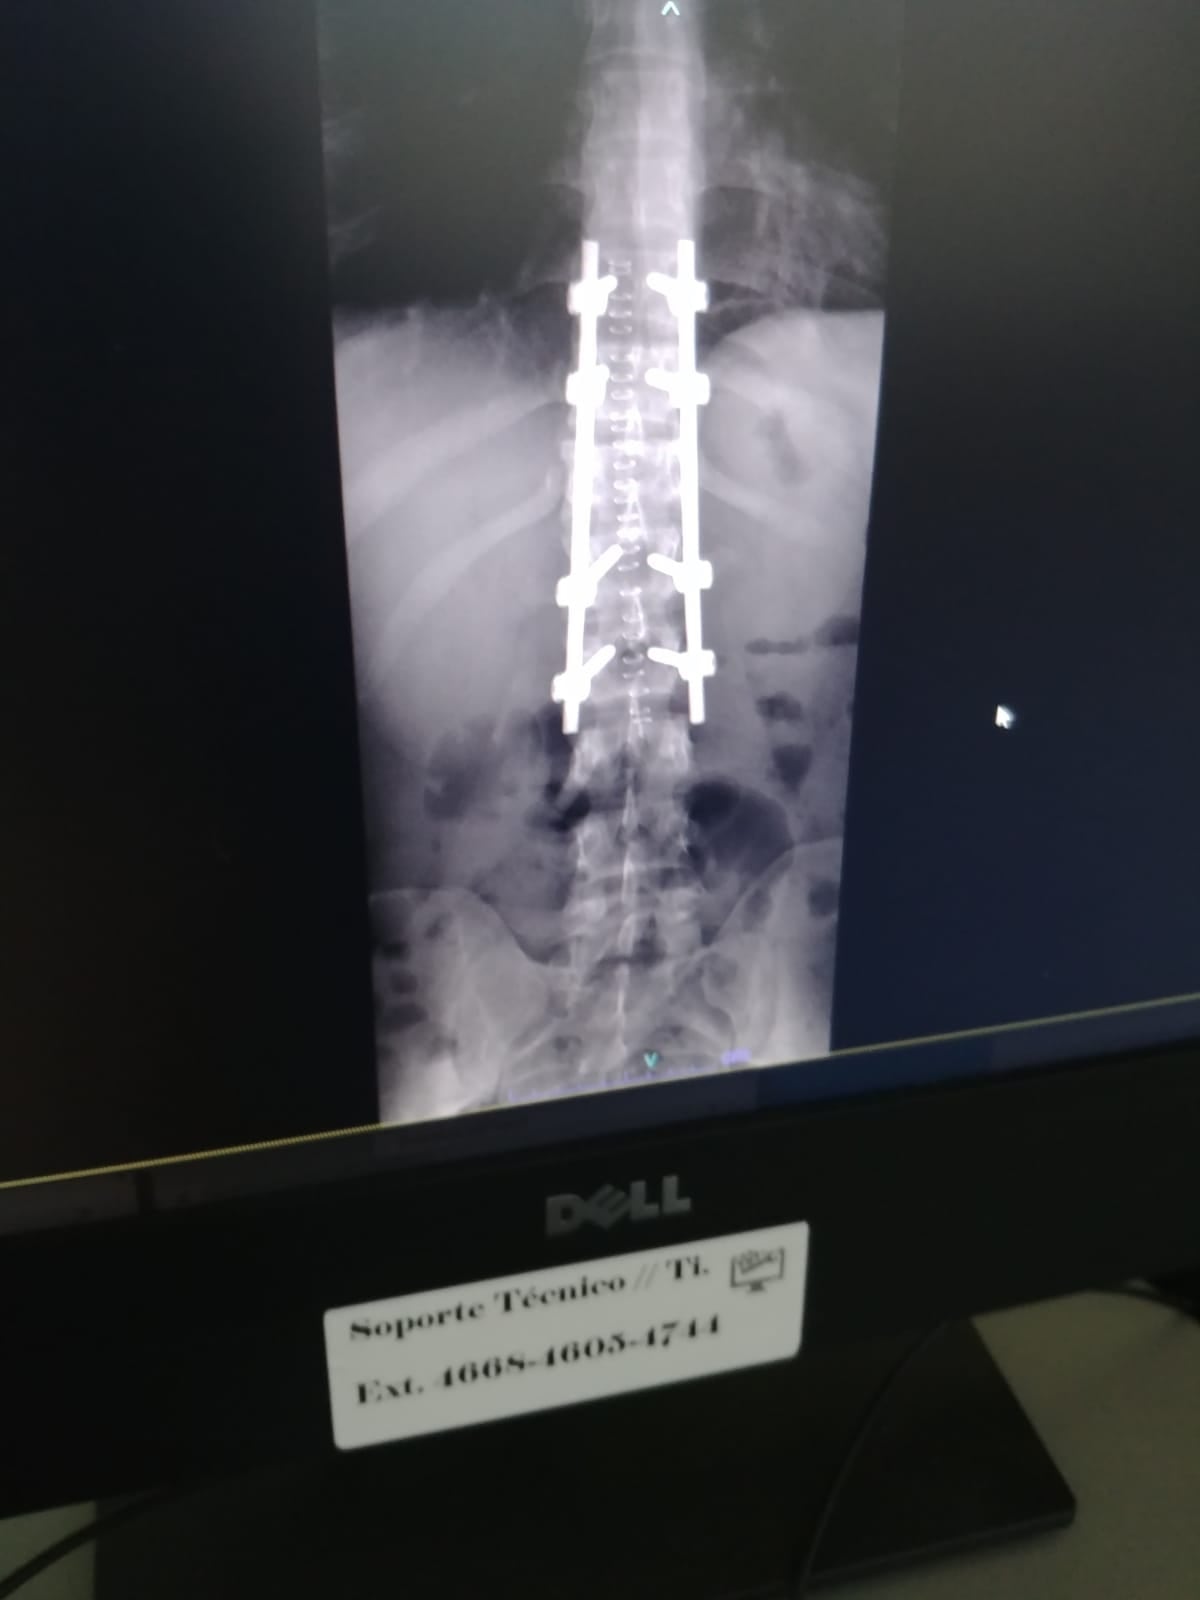

Quesada sufrió una fractura en tres vertebras de la columna y por tal motivo tuvieron que hacerle una delicada operación en la que le colocaron varias placas, afortunadamente todo salió bien y pudo regresar a su trabajo en setiembre.